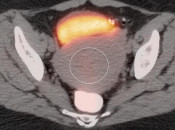

Case 3 (Image 2)

Fused axial image demonstrates intense metabolic activity involving the endometrium. The CT image demonstrates mild associated distension of the endometrial cavity. As this patient is postmenopausal, this is suspicious for malignancy (biopsy-proven endometrial carcinoma).